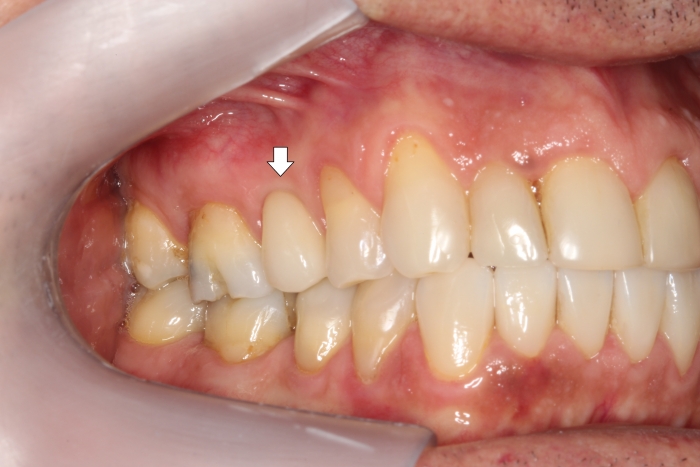

Provisório imediato

Dente definitivo